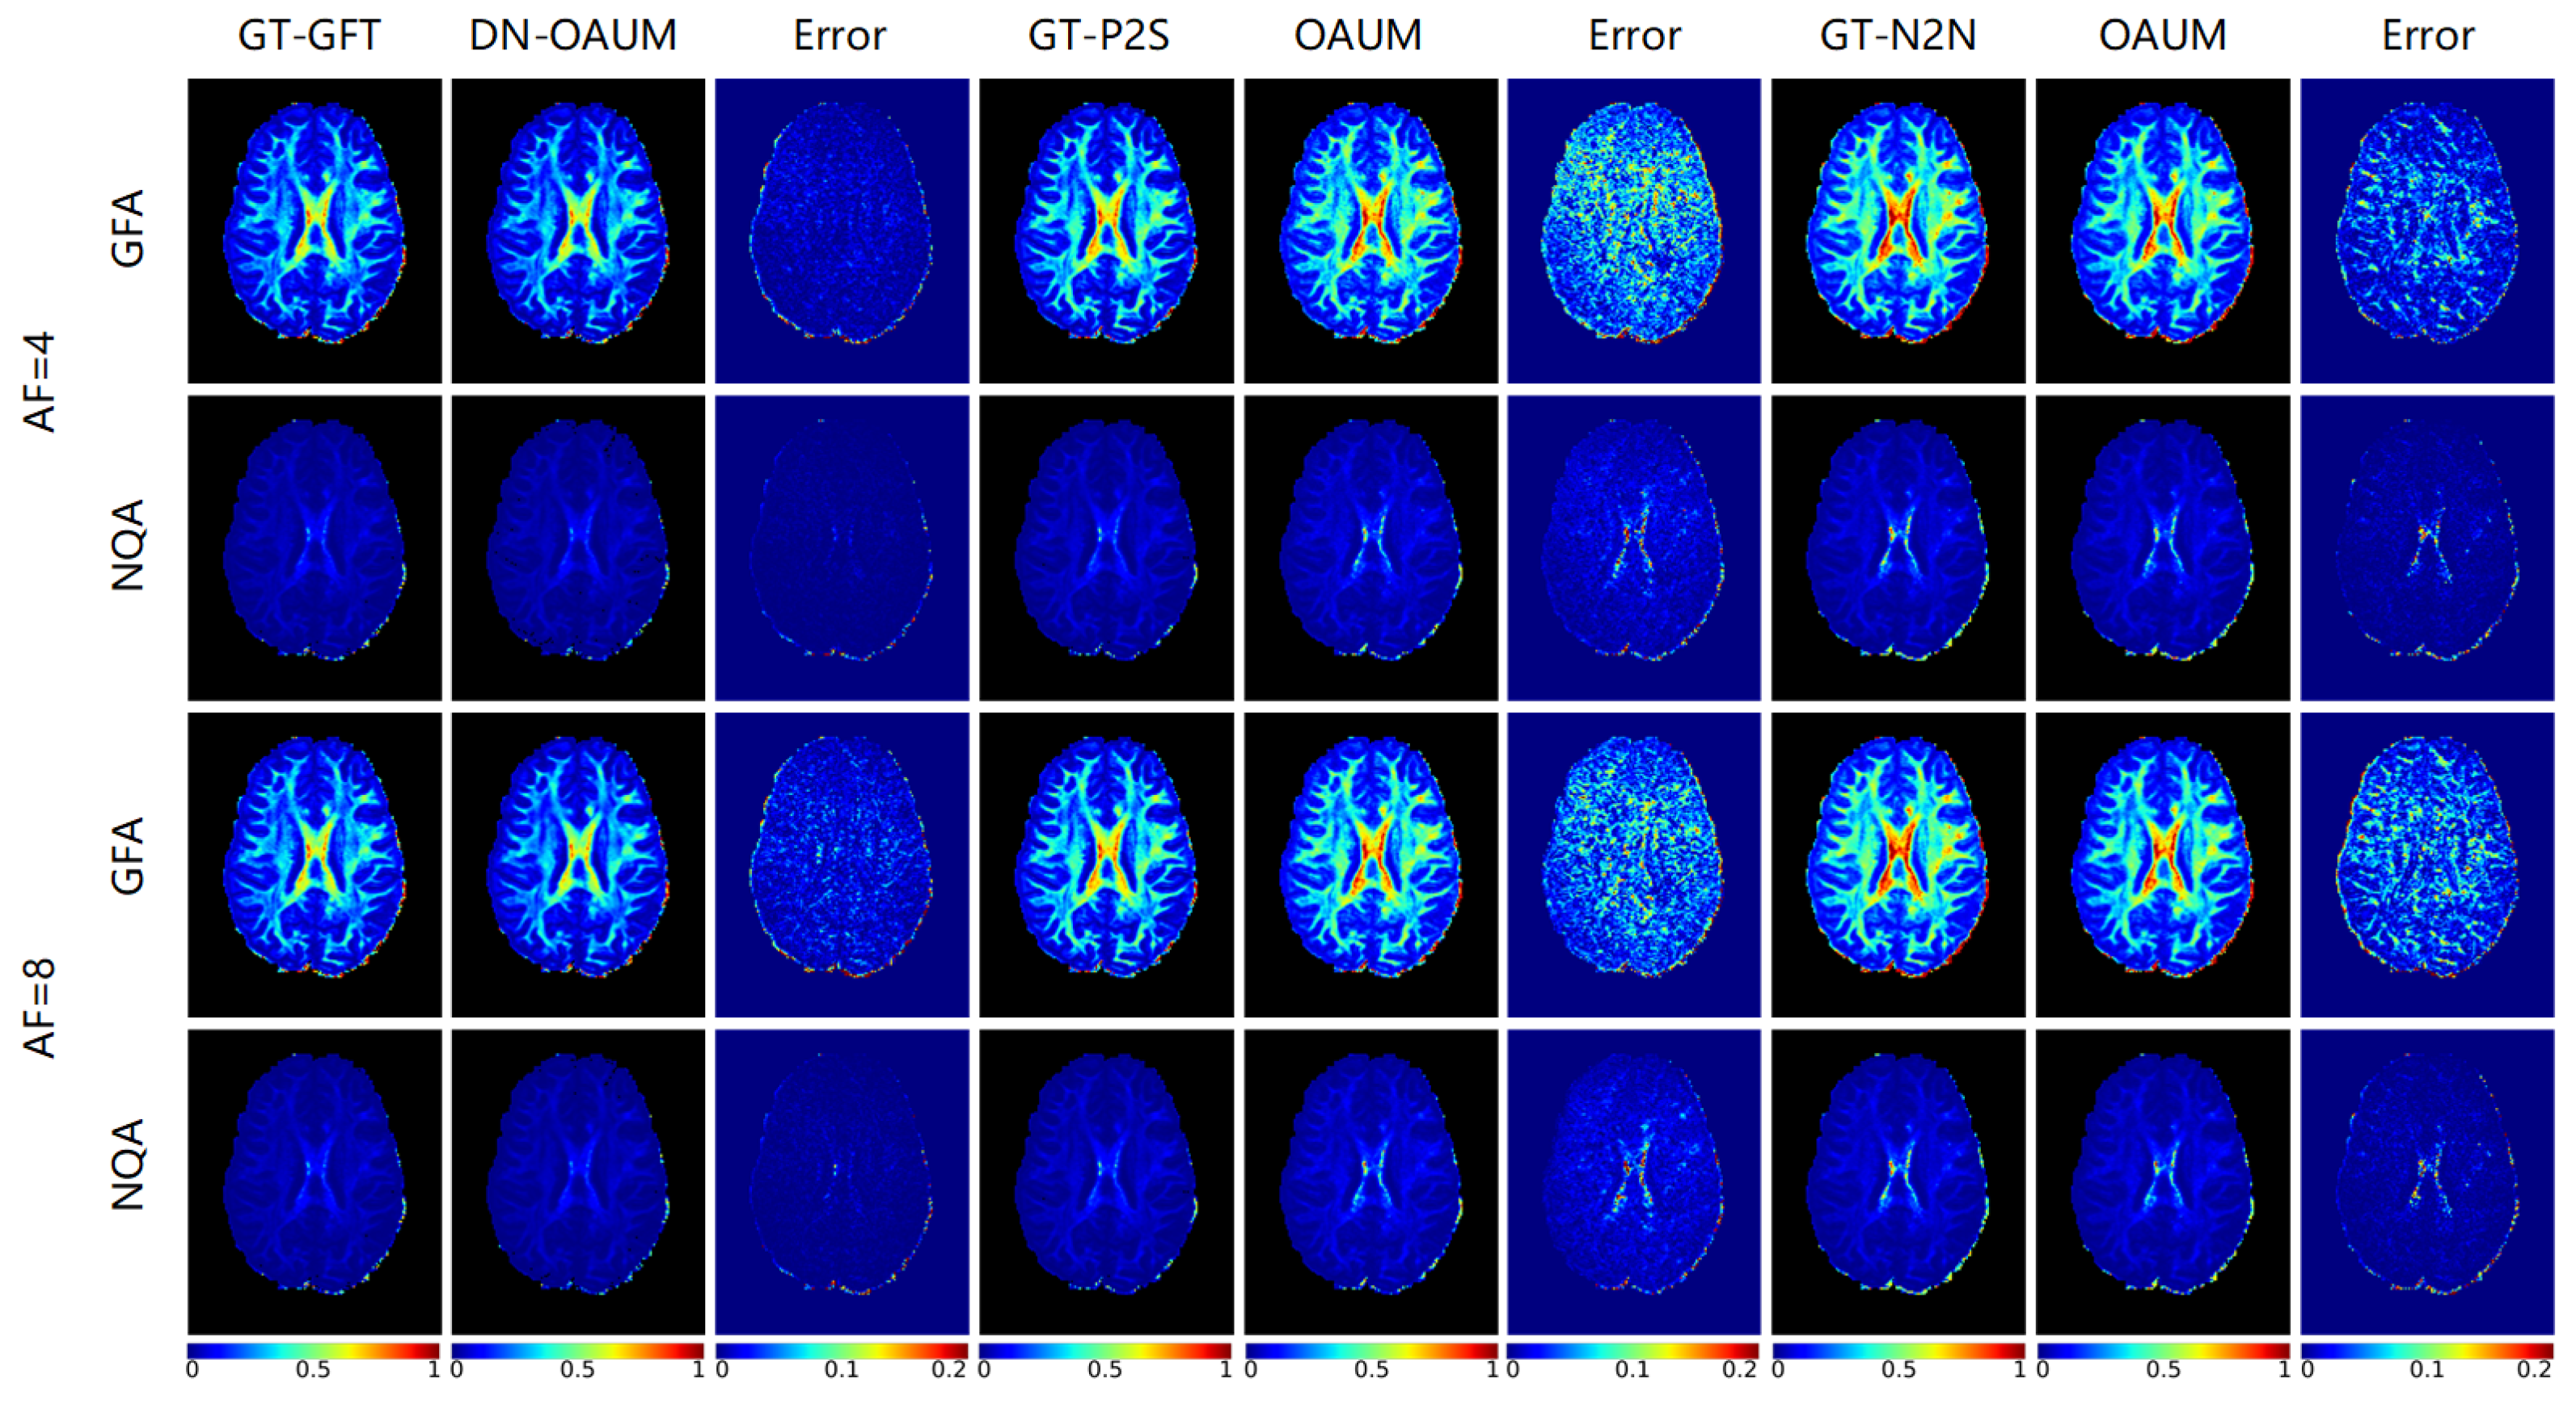

Figure 10 shows reconstructed DWIs using various methods with k-q space joint fast reconstruction on input noisy k-space undersampled data under 4-fold and 8-fold acceleration factors. The figure also includes their corresponding residual maps and zoomed-in maps. For the DN-OAUM method, the denoised result of original noisy DWIs obtained by GFT was used as the reference standard, i.e., the first column in the figure (GT-GFT). To preprocess denoised data for network training, Patch2Self and Neighbor2Neighbor methods were used for OAUM method. GT-P2S and GT-N2N represent data preprocessed using the Patch2Self and Neighbor2Neighbor methods for denoising, respectively, and their corresponding reconstructed DWIs after network training are shown on the right side. Similar to the above figures, two gradient directions’ results (Dir.1 and Dir.2) are displayed for each method to reflect both the k-space reconstruction effect and q-space reconstruction effect of networks. Observing the results in the Dir.1 gradient direction first shows that DN-OAUM reconstructed clear and smooth DWIs with very little visual difference from GT-GFT even when zoomed in significantly. However, OAUM trained using GT-P2S data preprocessing contained obvious noise points in its reconstructed DWIs; when observing zoomed-in regions compared to GT-P2S, they cover an additional layer of granular noise while image details became blurred due to the noise influence. Similarly, OAUM trained using GT-N2N also contained noise points in its reconstructed DWIs. Combining error maps revealed that DN-OAUM had minimal reconstruction errors among all methods in the Dir.1 direction with better image quality, while there were significant differences between the OAUM results using different denoising preprocessing techniques.

Upon examining the label data for each method in Figure 10, it is evident that GT-GFT and GT-P2S had fewer instances of visual noise compared to GT-N2N. Consequently, when training OAUM to reconstruct k-space with noisy data using GT-N2N, both the reconstructed result and label contained similar noise, resulting in relatively small errors. However, when using GT-P2S for training OAUM, there was no apparent noise in its label. Nevertheless, upon reconstructing k-space with data affected by noise, its reconstructed result contained a significant amount of noise, which differed significantly from that of GT-P2S. Therefore, this method performs exceptionally well on k-space reconstruction and can produce high-quality DWIs without significant visual noise compared to GT-GFT while minimizing error.

Upon observing the reconstructed DWIs in the gradient direction of Dir.2, the DN-OAUM method yielded clearly superior image quality. Although visually appealing, the OAUM method trained on GT-P2S data exhibited small particle-like noise when scrutinized under zoomed-in areas. Conversely, OAUM based on GT-N2N data produced blurry DWIs that lacked detail. Error maps corroborate these findings by demonstrating that DN-OAUM’s reconstruction results in the Dir.2 gradient direction were optimal. To better quantify image quality, we conducted a quantitative analysis comparison on reconstructed DWIs as presented in Table 6. The results indicate that the DN-OAUM method outperformed the other comparative methods in terms of quantitative indicators.

The results of visualizing DWIs reconstructed using various methods under an acceleration factor of 8 are also presented in Figure 10. In the gradient direction Dir.1, the DN-OAUM method showed clear details in the DWIs, while the OAUM method was severely affected by noise. Similarly, for an acceleration factor of 8 in the Dir.2 gradient direction, the DN-OAUM method produced better image quality than the OAUM method. Table 6 provides quantitative results that show a decrease in the RMSE and an improvement in the PSNR and SSIM with the DN-OAUM method compared to the OAUM method.

The results of the GFA and NQA parameter visualization, calculated from reconstructed HARDI data using the above methods under 4-fold and 8-fold acceleration factors, are presented in Figure 12. Clearly, the DN-OAUM method had smaller errors in both GFA and NQA compared to the two OAUM methods trained with denoising preprocessed data. The latter had larger errors due to noise interference. These findings are supported by quantitative results in Table 8 and Table 9, leading to a conclusion that DN-OAUM outperforms OAUM regarding GFA and NQA. Thus, it can be concluded that the denoising effect of the DN-OAUM method is not only effective on DWIs but also has practical significance for diffusion parameter reconstruction.

Figure 10. DWIs reconstructed by different methods using noisy data at different acceleration factors.

Figure 12. The parametric maps estimated from DWIs at different acceleration factors.